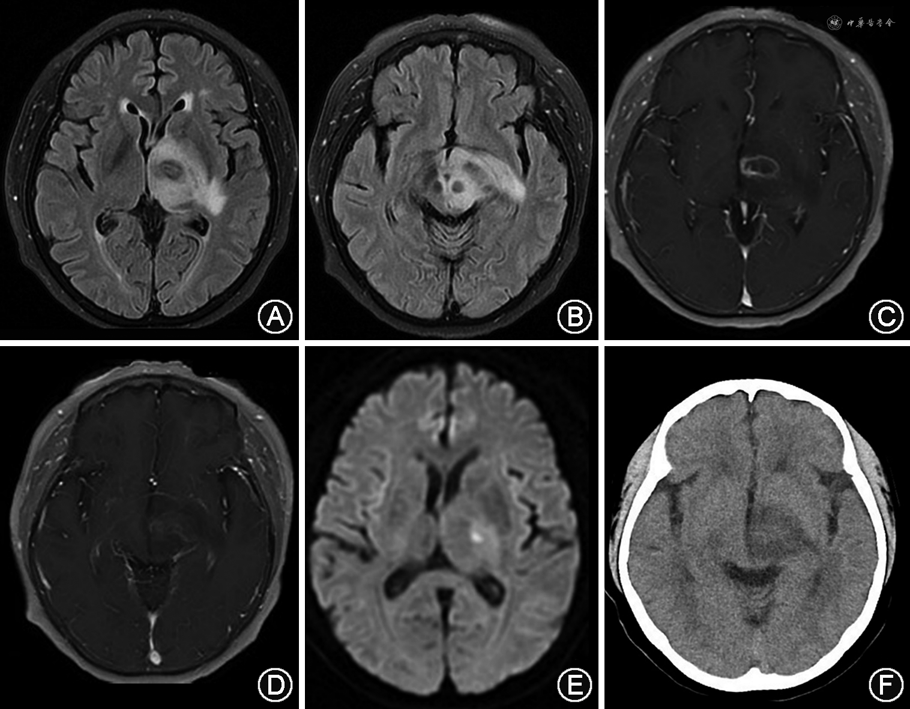

影像学检查:头颅CT(2022年4月1日)示左侧中脑、丘脑及基底节低密度影。头颅MRI(2022年4月2日)示左侧中脑、丘脑及基底节异常信号,累及对侧中脑及视束,强化后可见环形强化病灶(图1)。

在影像学方面,淋巴瘤肿块通常在CT上表现为等密度或高密度肿块,相应病变在MRI的T1与T2加权像上均为低信号或等信号,在DWI则为稍高信号,这是因为肿瘤细胞致密排列且核质比较高。免疫功能正常患者的淋巴瘤与PTLD的病理学差异,亦可在影像学有所体现。免疫功能正常患者强化MRI的特征性表现为均匀一致的实性强化,而免疫缺陷患者则因肿瘤的中心性坏死表现为环形强化,如合并出血,则T1加权像可能出现高信号,T2加权像相应为低信号[11, 12, 13]。